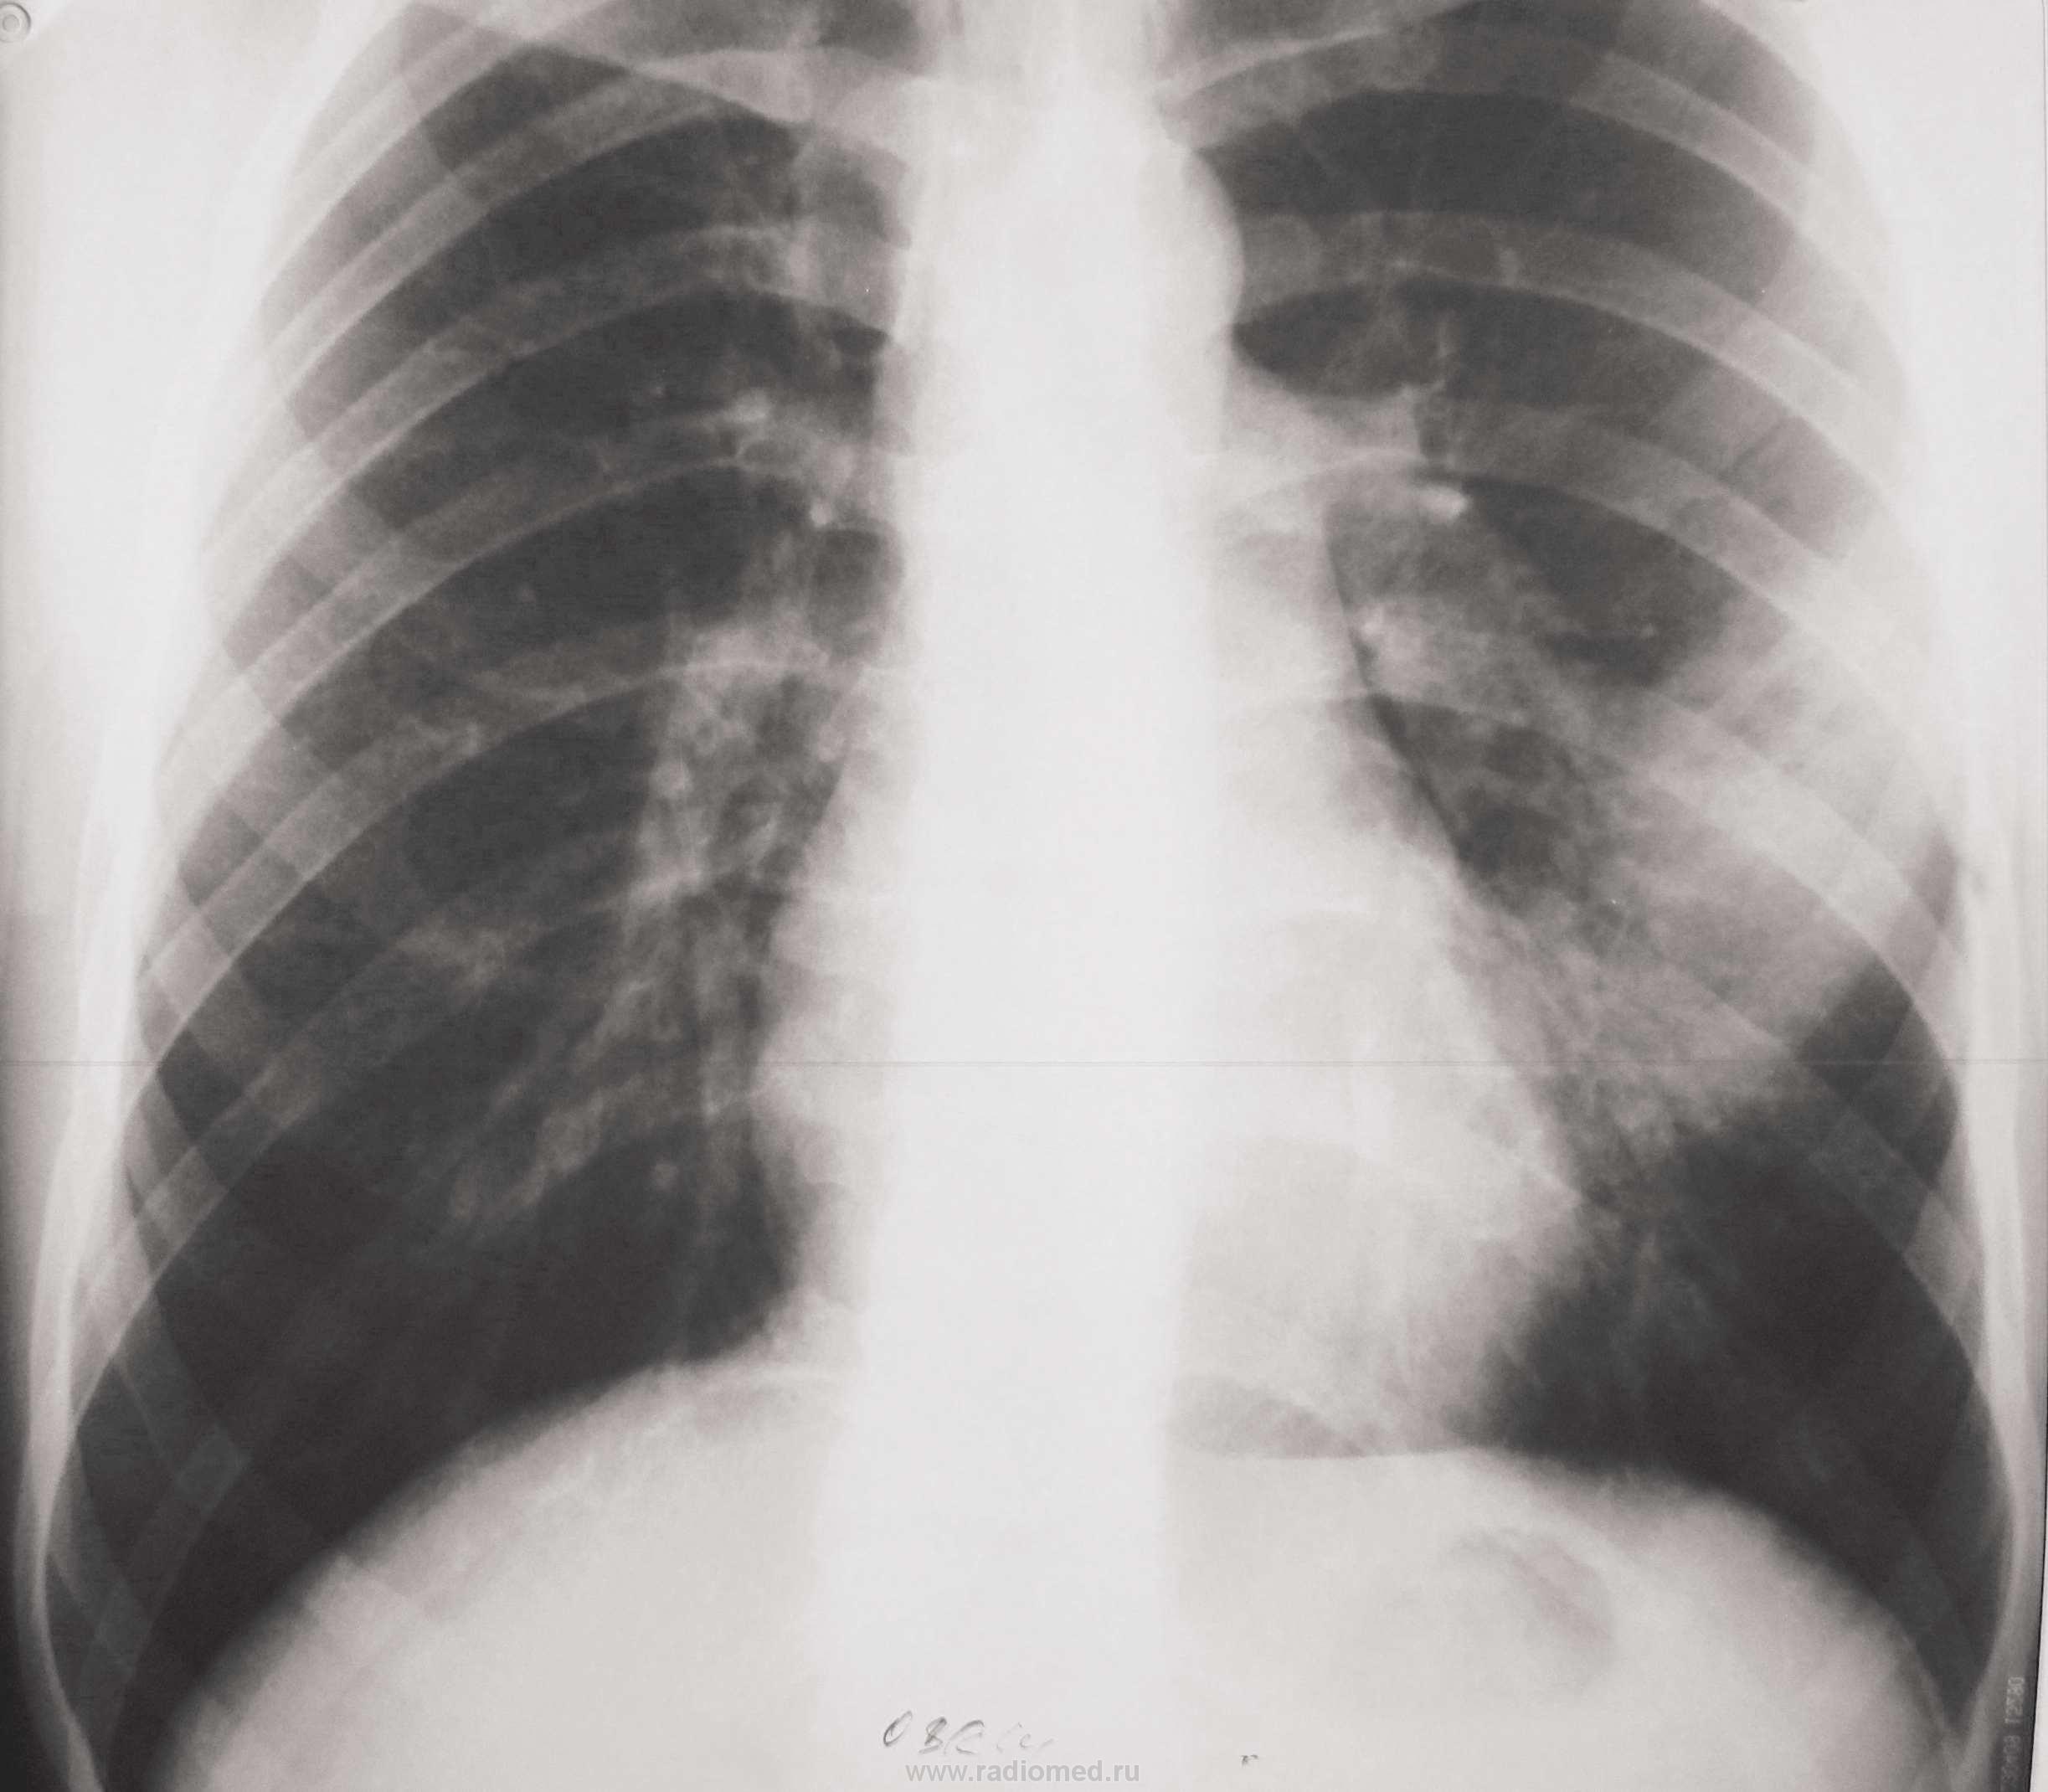

Молодой человек поступил в инфекционное отделени с тонзилитом. В день поступления флю - норма. Явления тонзилита прошли, но температура не снижалась. Сделали повторную флю и выставили пневмонию. Выставляю флюорограммы с интервалом в 1 неделю. Данные изменения держатся месяц без како-либо динамики. В анализах только повышенное СОЭ, колеблется от 20 до 38. В плане КТ.

Публикации: 2324

Молодому человеку 20 лет. Снимки разместил по порядку с периодичностью в неделю. С момента поступления прошло полтора месяца. За это время, после инфекционного отделения, лечился в туберкулёзном, а после в пульмонологии (до настоящего времени).Последние рентгенограммы сделаны 2,04., а томограммы 4.04. По поводу кругляшки, особенно после туб.отд., думаю, что может выскочить и ТБЦ. Такое уже было, правда там был распад.

Фтизиатры своё исключили. Поэтому он и оказался в пульмонологии. Флюшка от 1 марта чистая.

Какой интересный междолевой плеврит.

Левосторонняя S4-S5 пневмония, осложненная абсцедированием.По пятому по счету снимку явно на фоне инфильтрации видны зоны распада.А впоследствии и абсцесс сформировался-ТМГ тому подтверждение.Отдавайте торакалистам .